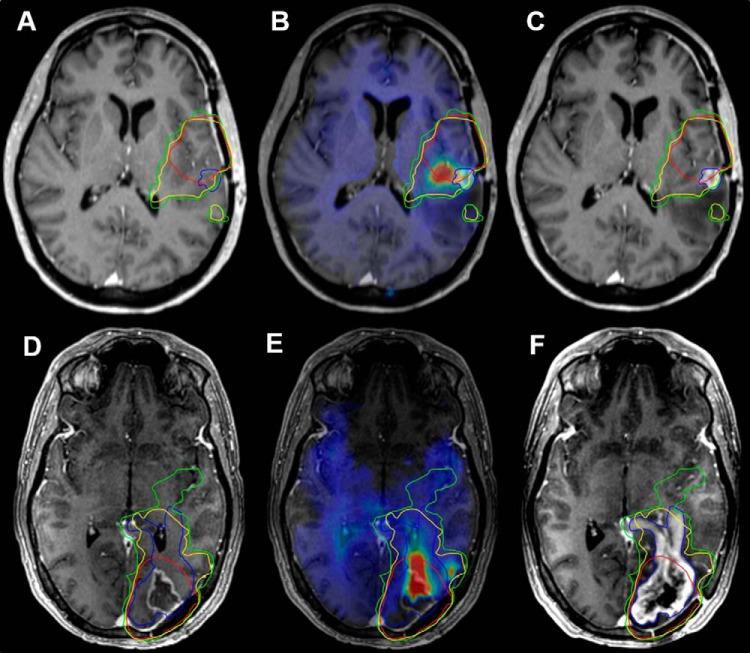

Due to glioblastoma's infiltrative nature, an optimal radiation therapy (RT) plan requires targeting infiltration not identified by anatomical magnetic resonance imaging (MRI). Here, high-resolution, whole-brain spectroscopic MRI (sMRI) is used to describe tumor infiltration alongside anatomical MRI and simulate the degree to which it modifies RT target planning. In 11 patients with glioblastoma, data from preRT sMRI scans were processed to give high-resolution, whole-brain metabolite maps normalized by contralateral white matter. Maps depicting choline to N-Acetylaspartate (Cho/NAA) ratios were registered to contrast-enhanced T1-weighted RT planning MRI for each patient. Volumes depicting metabolic abnormalities (1.5-, 1.-, and 2.0-fold increases in Cho/NAA ratios) were compared with conventional target volumes and contrast-enhancing tumor at recurrence. sMRI-modified RT plans were generated to evaluate target volume coverage and organ-at-risk dose constraints. Conventional clinical target volumes and Cho/NAA abnormalities identified significantly different regions of microscopic infiltration with substantial Cho/NAA abnormalities falling outside of the conventional 60 Gy isodose line (41.1, 22.2, and 12.7 cm, respectively). Clinical target volumes using Cho/NAA thresholds exhibited significantly higher coverage of contrast enhancement at recurrence on average (92.4%, 90.5%, and 88.6%, respectively) than conventional plans (82.5%). sMRI-based plans targeting tumor infiltration met planning objectives in all cases with no significant change in target coverage. In 2 cases, the sMRI-modified plan exhibited better coverage of contrast-enhancing tumor at recurrence than the original plan. Integration of the high-resolution, whole-brain sMRI into RT planning is feasible, resulting in RT target volumes that can effectively target tumor infiltration while adhering to conventional constraints.